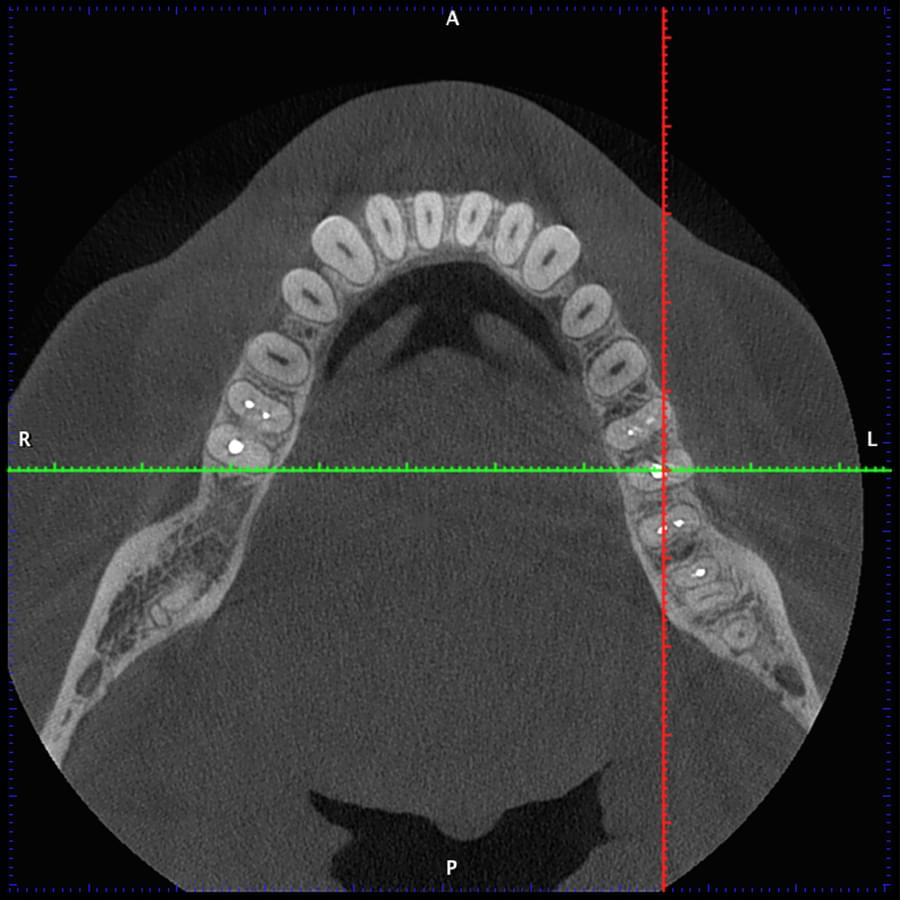

Комп'ютерна томографія

Щелепно-лицева діагностика

Мережа діагностичних центрів "МАЙРЕЙ ЛАБ" забезпечує точну та надійну діагностику

щелепно-лицевої ділянки з мінімальним ризиком для пацієнтів.